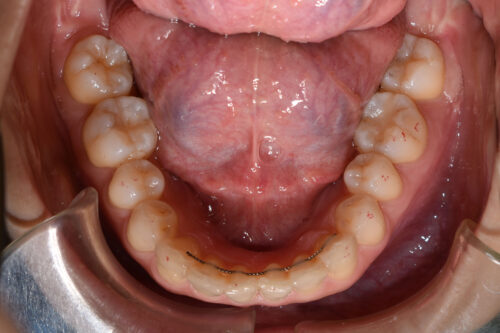

初診時年齢 30歳 女性

過蓋咬合と

叢生(歯ならびの デコボコ)

を主訴に

池袋よりひとつ隣駅の東京都豊島区大塚駅すぐの大塚たまみ矯正歯科へ

いらっしゃいました。

下の歯が 全く見えない状態で

上下の歯が 翼のように ガタついて(翼状捻転)いる

状態でした。

ワイヤー矯正治療10か月後です。